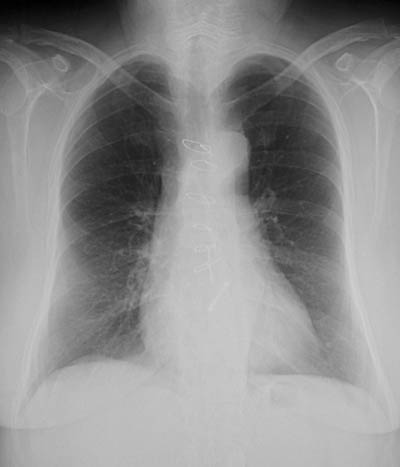

![]() | The chest radiograph above in lateral view reveals the presence of a bileaflet tilting disk mechanical aortic valve prosthesis. Note that the two leaflets are open and seen on edge. In the PA view below, the metal ring can be seen to the lower left of the sternotomy wires. |